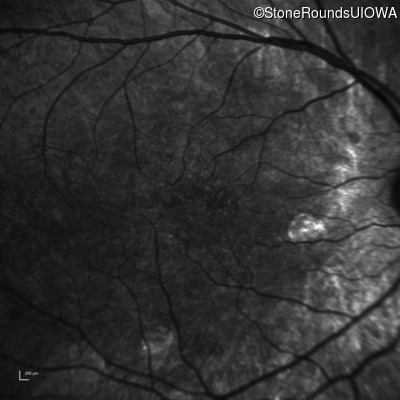

Infrared Fundus Photograph - Right - 20/50 +1 sc

Exemplar